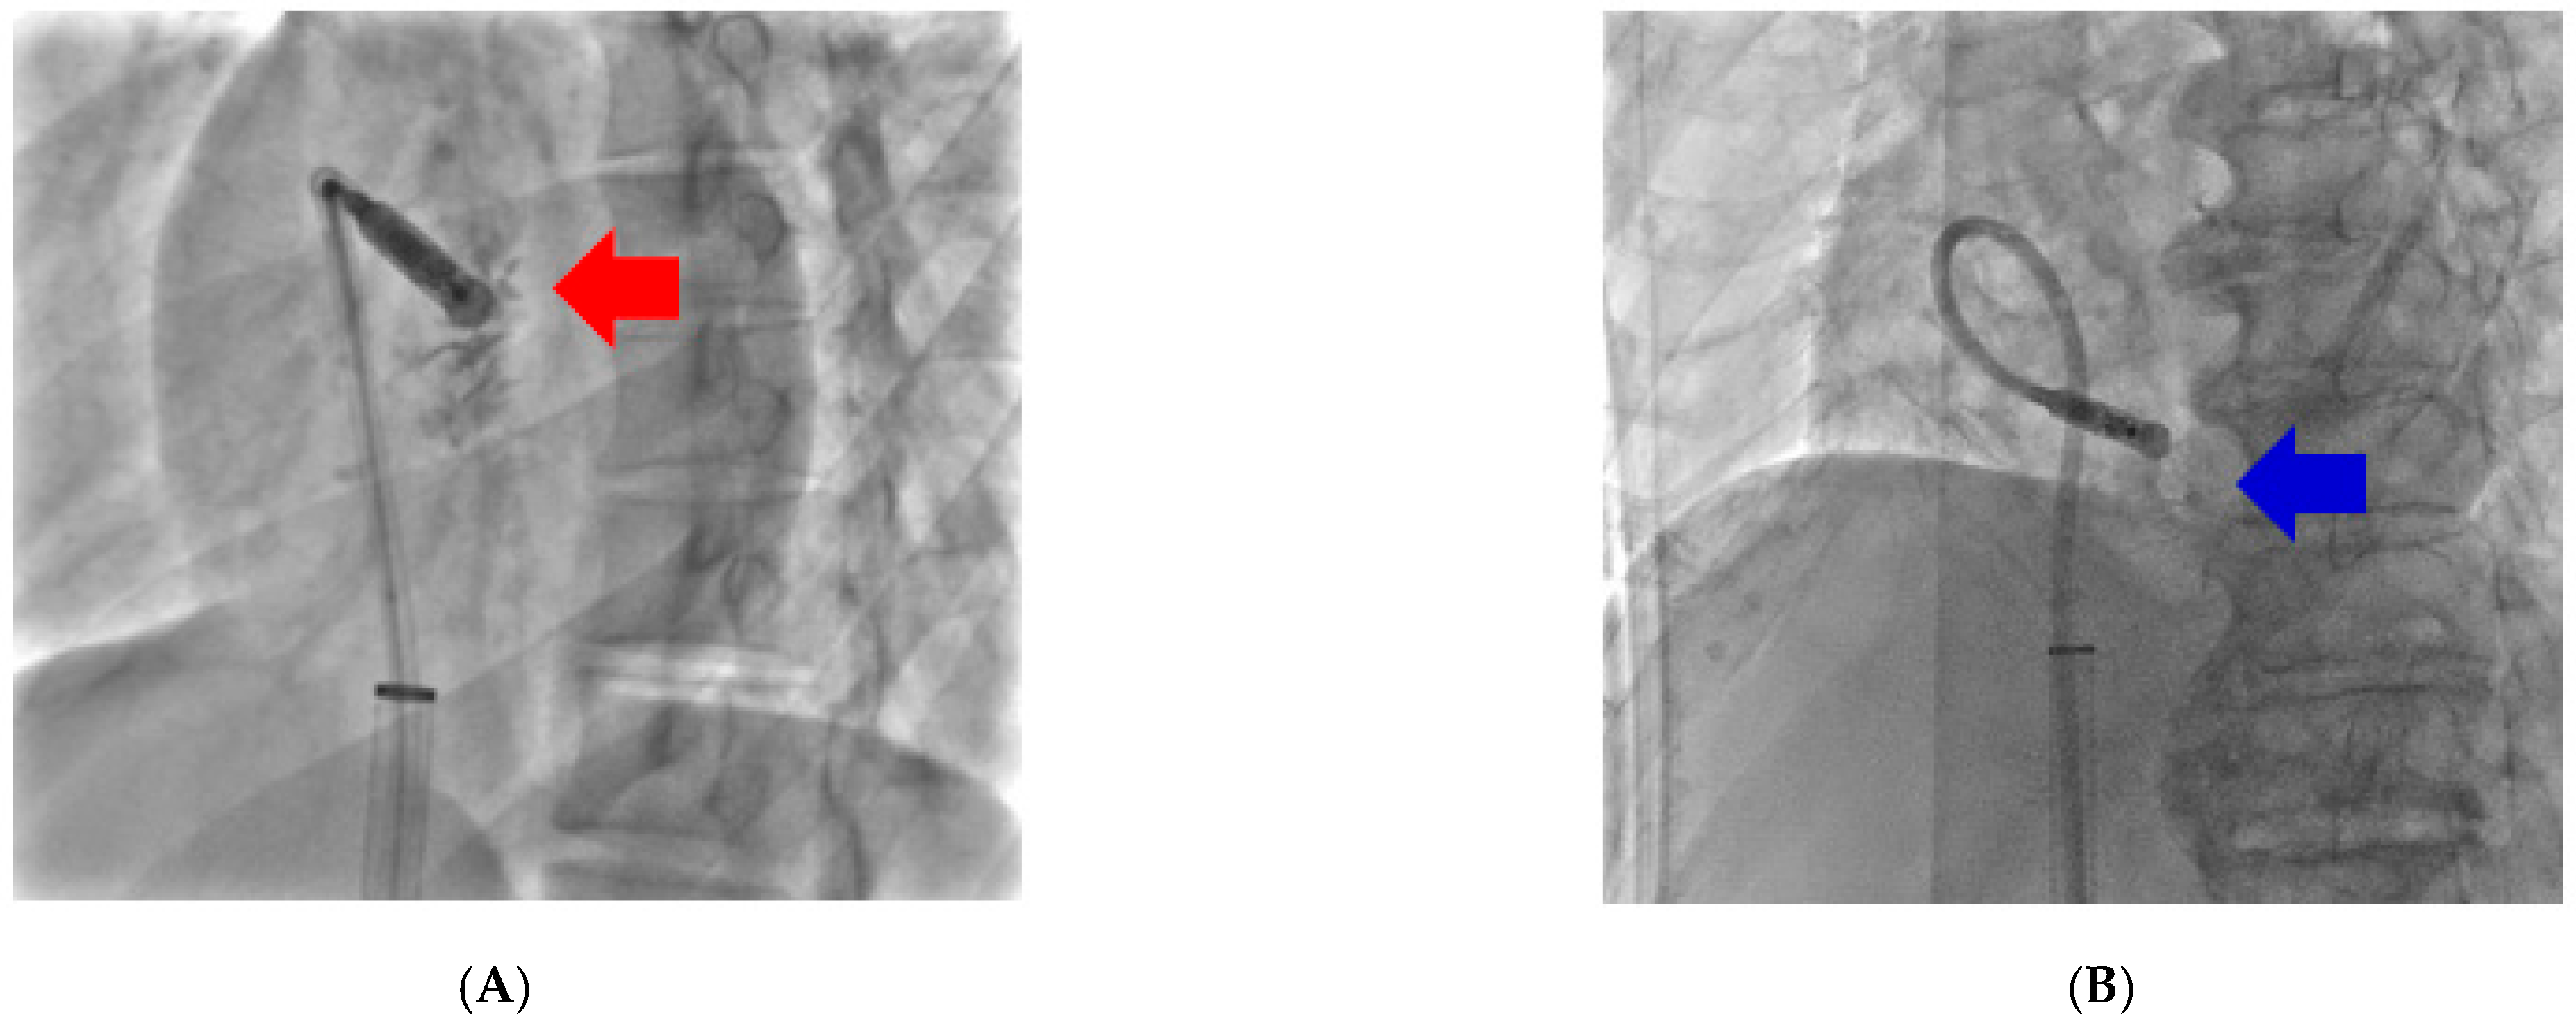

- Li, Y.; Xing, Q.; Xiaokereti, J.; Chen, C.; Zhang, J.; Zhou, X.; Lu, Y.; Tuerhong, Z.; Tang, B. Right ventriculography improves the accuracy of leadless pacemaker implantation in right ventricular mid-septum. J. Interv. Card. Electrophysiol. 2023, 66, 941–949. [Google Scholar] [CrossRef] [PubMed] [PubMed Central]